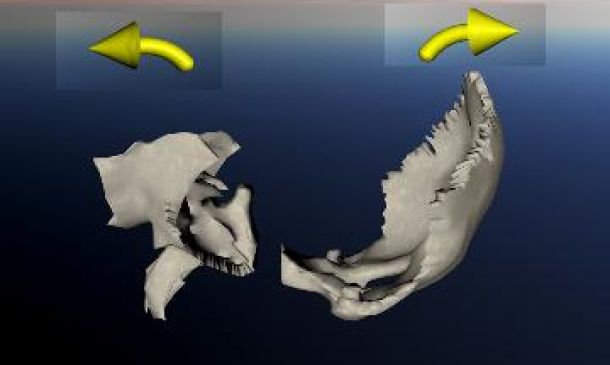

ΣΦΗΝΟΪΝΙΑΚΗ ΕΝΩΣΗ: Σύμφυση vs Συνχόνδρωση

Σύμφωνα με τον Dr. Sutherland, το Σφηνοειδές και το Ινιακό οστό παίζουν ένα σημαντικό ρόλο στη κινητικότητα των οστών του κρανίου. Ενώνονται με την Σφηνοϊνιακή άρθρωση. Το Σφηνοειδές οστό είναι το κλειδί της κίνησης και το Ινιακό το ακολουθεί, κάτι που συμβαίνει και με τα υπόλοιπα οστά του κρανίου. Το ίδιο ισχύει και για το Ιερό οστό, το οποίο επηρεάζεται από τη κίνηση του Ινιακού μέσω του σπονδυλικού σωλήνα (dura tube).